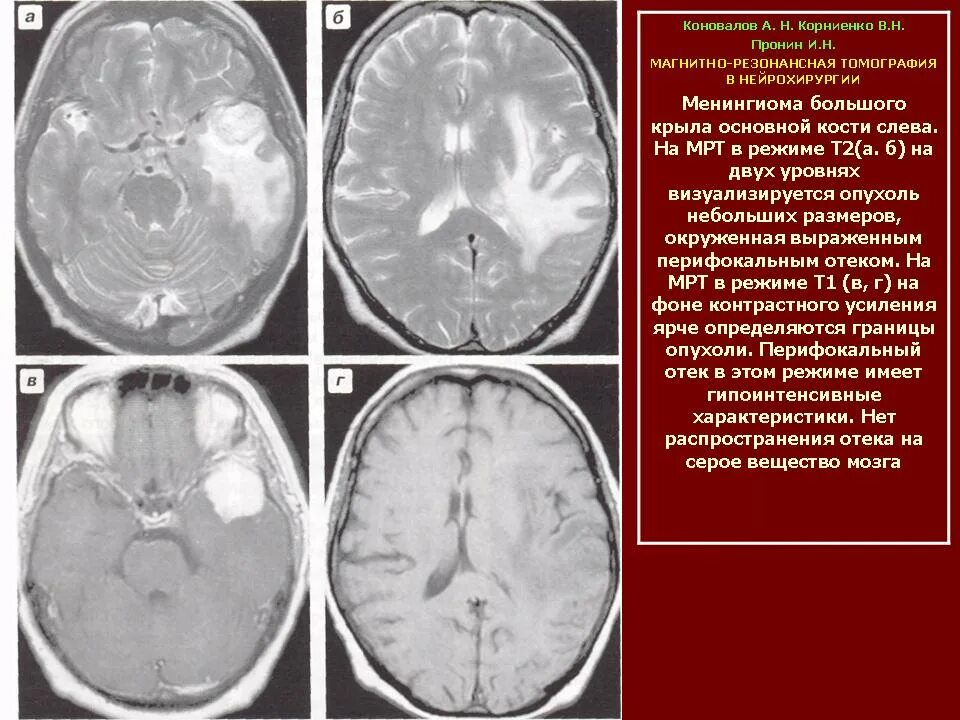

Перифокальный отек образования